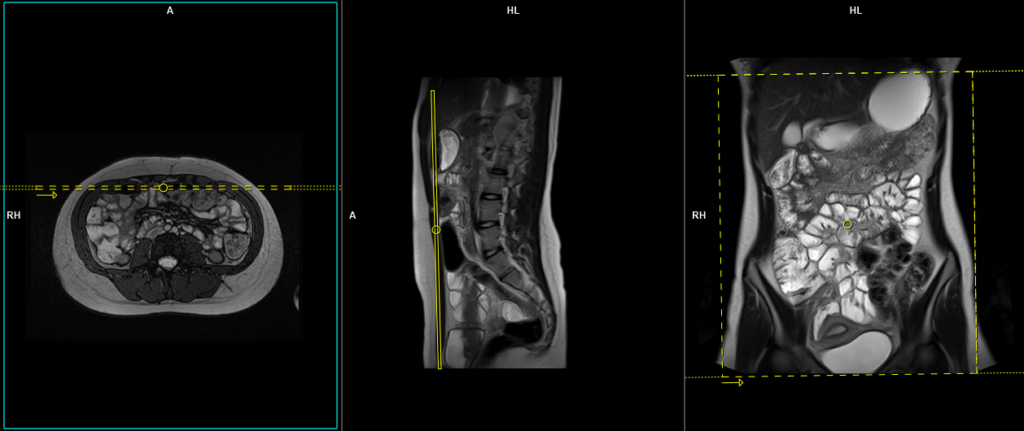

T2 HASTE 4 mm axial

Plan the axial slices on the coronal image, position the block horizontally across the abdomen as shown, and ensure that the positioning block is also checked in the other two planes. Establish an appropriate angle horizontally across the abdomen in the sagittal plane. The slices must be sufficient to cover the entire abdomen and pelvis from the stomach to the pubic symphysis. Phase oversampling can be used to avoid wrap-around artifacts. Instruct the patient to hold their breath during image acquisition.

The axial scan is performed as two separate blocks with a 20-30% slice overlap between them. The scan is performed this way to avoid any RF inhomogeneity-related artifacts by conducting the scans at the isocenter of the magnet. Use the composing function in the scanner to stitch the two blocks together.

Protocol Parameters HASTE Axial

TR 2000-2500 | TE 90-100 | FLIP 150 | NEX 1 | SLICE 4 MM | MATRIX 320X320 | FOV 400-450 | PHASE A>P | OVERSAMPLE 0% | IPAT ON |